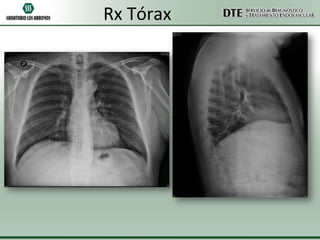

Rx Tórax